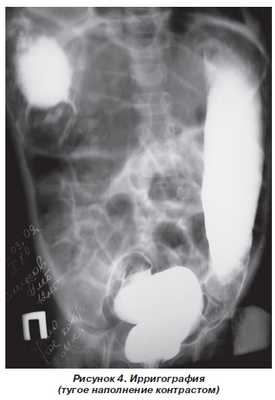

Произведена обзорная рентгенография брюшной полости, был выявлен гиперпневматоз тонкой и толстой кишки. Просвет толстой кишки расширен до 11 см с горизонтальным уровнем в мезогастрии справа. Под правым куполом диафрагмы газ в петле толстой кишки. Печень смещена книзу и медиально, ее верхний край на уровне Th11 (рис. 3).

При ирригоскопии от 31.03.09 г. контрастом выполнилась левая половина толстой кишки. Дальше контраст не проник. Участков аганглиоза нет (рис. 4).